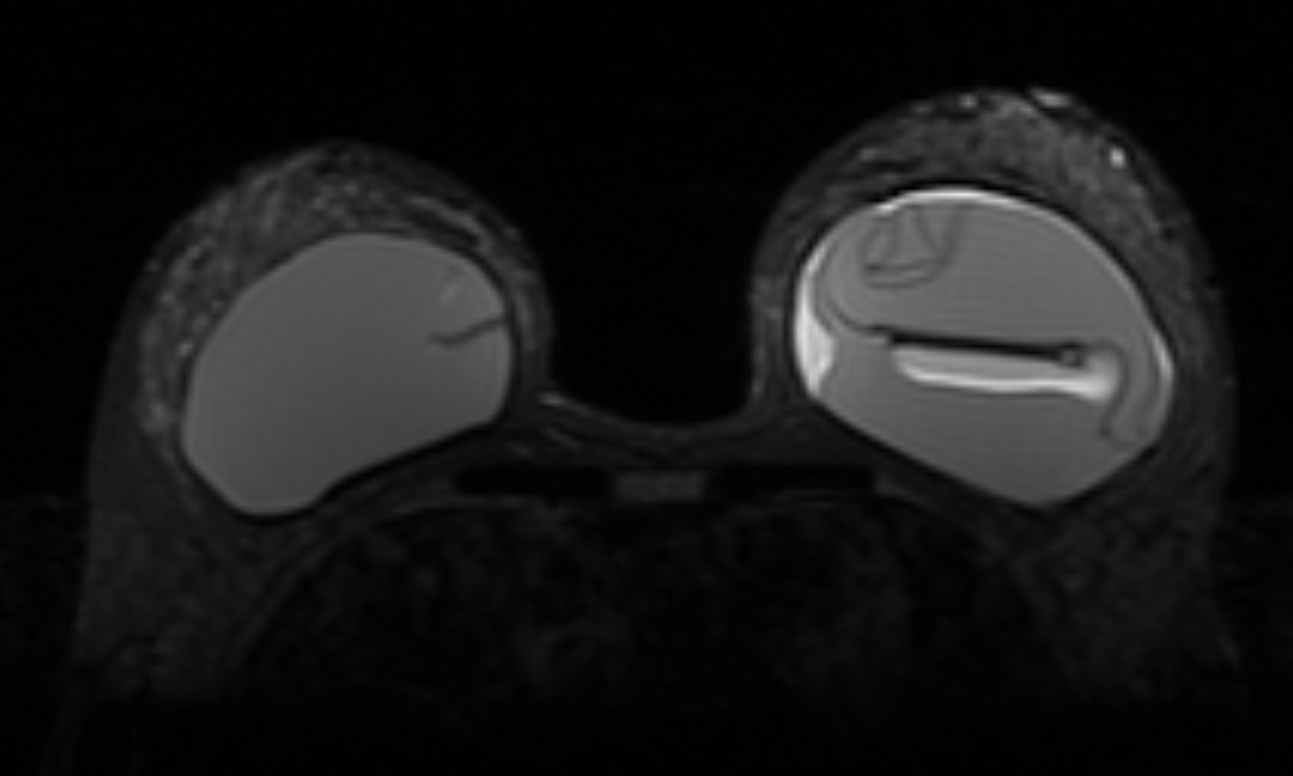

Gibbs ring artifact most noticable at implant interface (axial, IR sequence)

Gibbs ringing is a Fourier truncation artifact from finite k-space sampling. Inverse FFT of truncated data fails to represent the highest spatial frequencies at abrupt transitions, generating thin parallel bright/dark bands near high-contrast boundaries.

In breast MRI, it is easiest to see at skin-air, skin-parenchyma, and implant margins, especially in the phase-encode direction and on high-contrast sequences (e.g., T2). Reduce it by increasing phase-encode steps (more k-space lines) at scan-time cost; zero-fill interpolation can smooth the appearance but does not recover true spatial resolution. Recognition of the characteristic parallel-band pattern of Gibbs ringing helps differentiate it from true lesions.